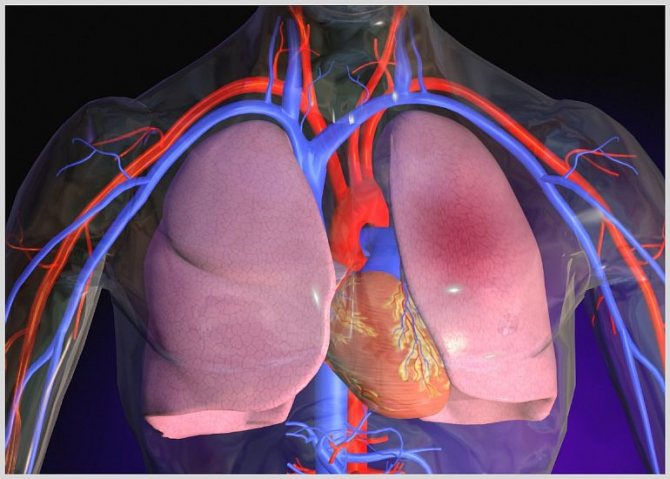

Кардиогенный тип возникает при недостаточности левого желудочка сердца и нарушении кровообращения в сосудах, которые участвуют в переносе крови от сердца к легким и наоборот. Основным причинами патологии являются: порок сердца, инфаркт миокарда, артериальная гипертензия, стенокардия. Для подтверждения диагноза пациентам измеряют давление в капиллярах легких, которое повышается выше 30 мм рт.ст. Чаще всего отек легких возникает у лежачих больных ночью.

К основным причинам данной патологии относятся: дефекты сердца и сосудов, миокардит, острая недостаточность левого желудочка, инфаркт миокарда, застой крови и пороки сердца.

Кардиогенный тип протекает быстро и времени на оказание первой помощи пациенту очень мало. Наибольший процент смертности приходится на этот вид.